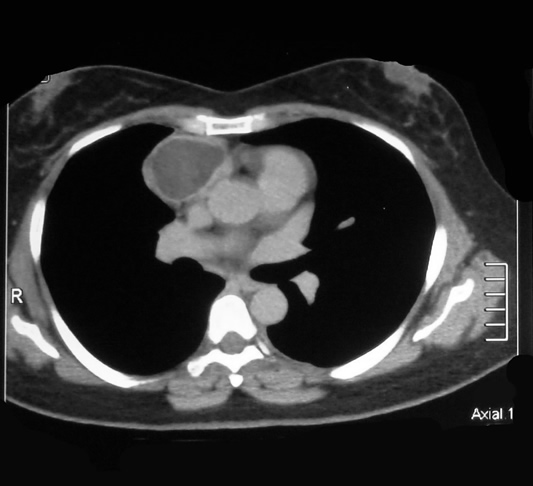

Corte Tomográfico ventana Mediastinal

Sección transversal a la altura del cono aórtico

Lesión capsulada de contenido homogéneo, redondeada, bien limitada, y en relación anterior a la vena pulmonar derecha, la vena cava superior y el cono aórtico, ocupando el seno costomediastinico anterior del hemitorax derecho.

El resto de la imagen de aspecto normal.

Sección transversal, a la altura de la aurícula derecha:

Lesión por delante del cono aórtico y en relación sobre la aurícula derecha y el cono , aórtico mantiene las características descritas además de una zona traslúcida en su interior.